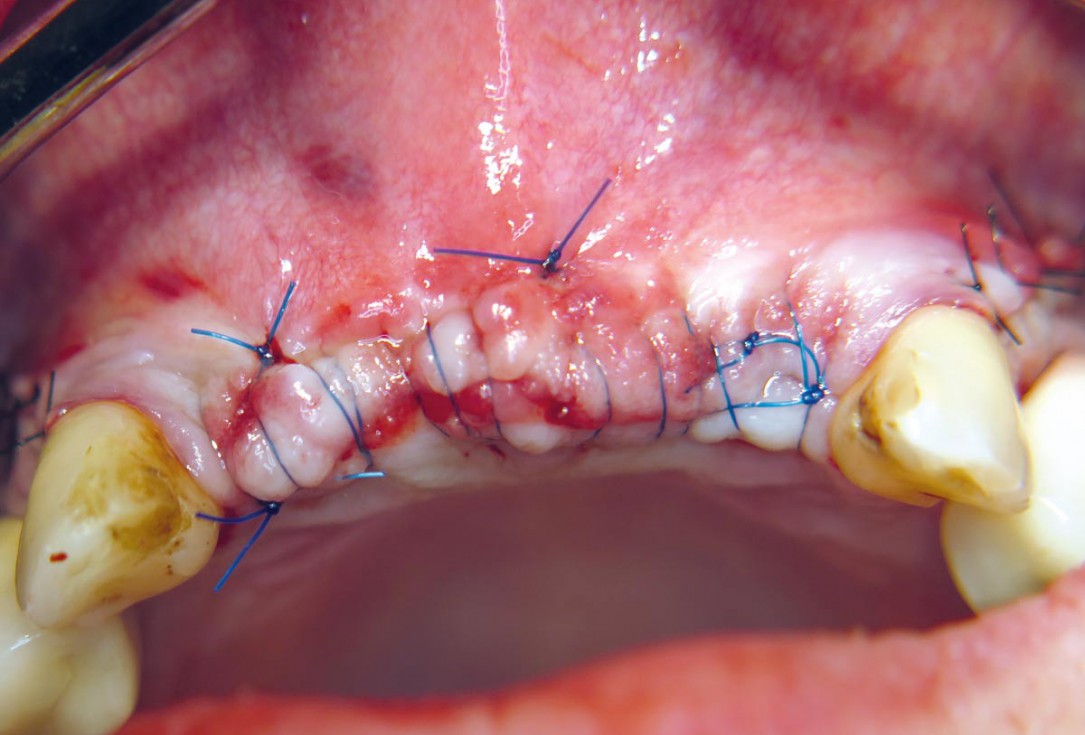

20 / 22 - Tension-free wound closure

Three-dimensional augmentation with maxgraft® cortico - M.Sc. E. Kapogianni